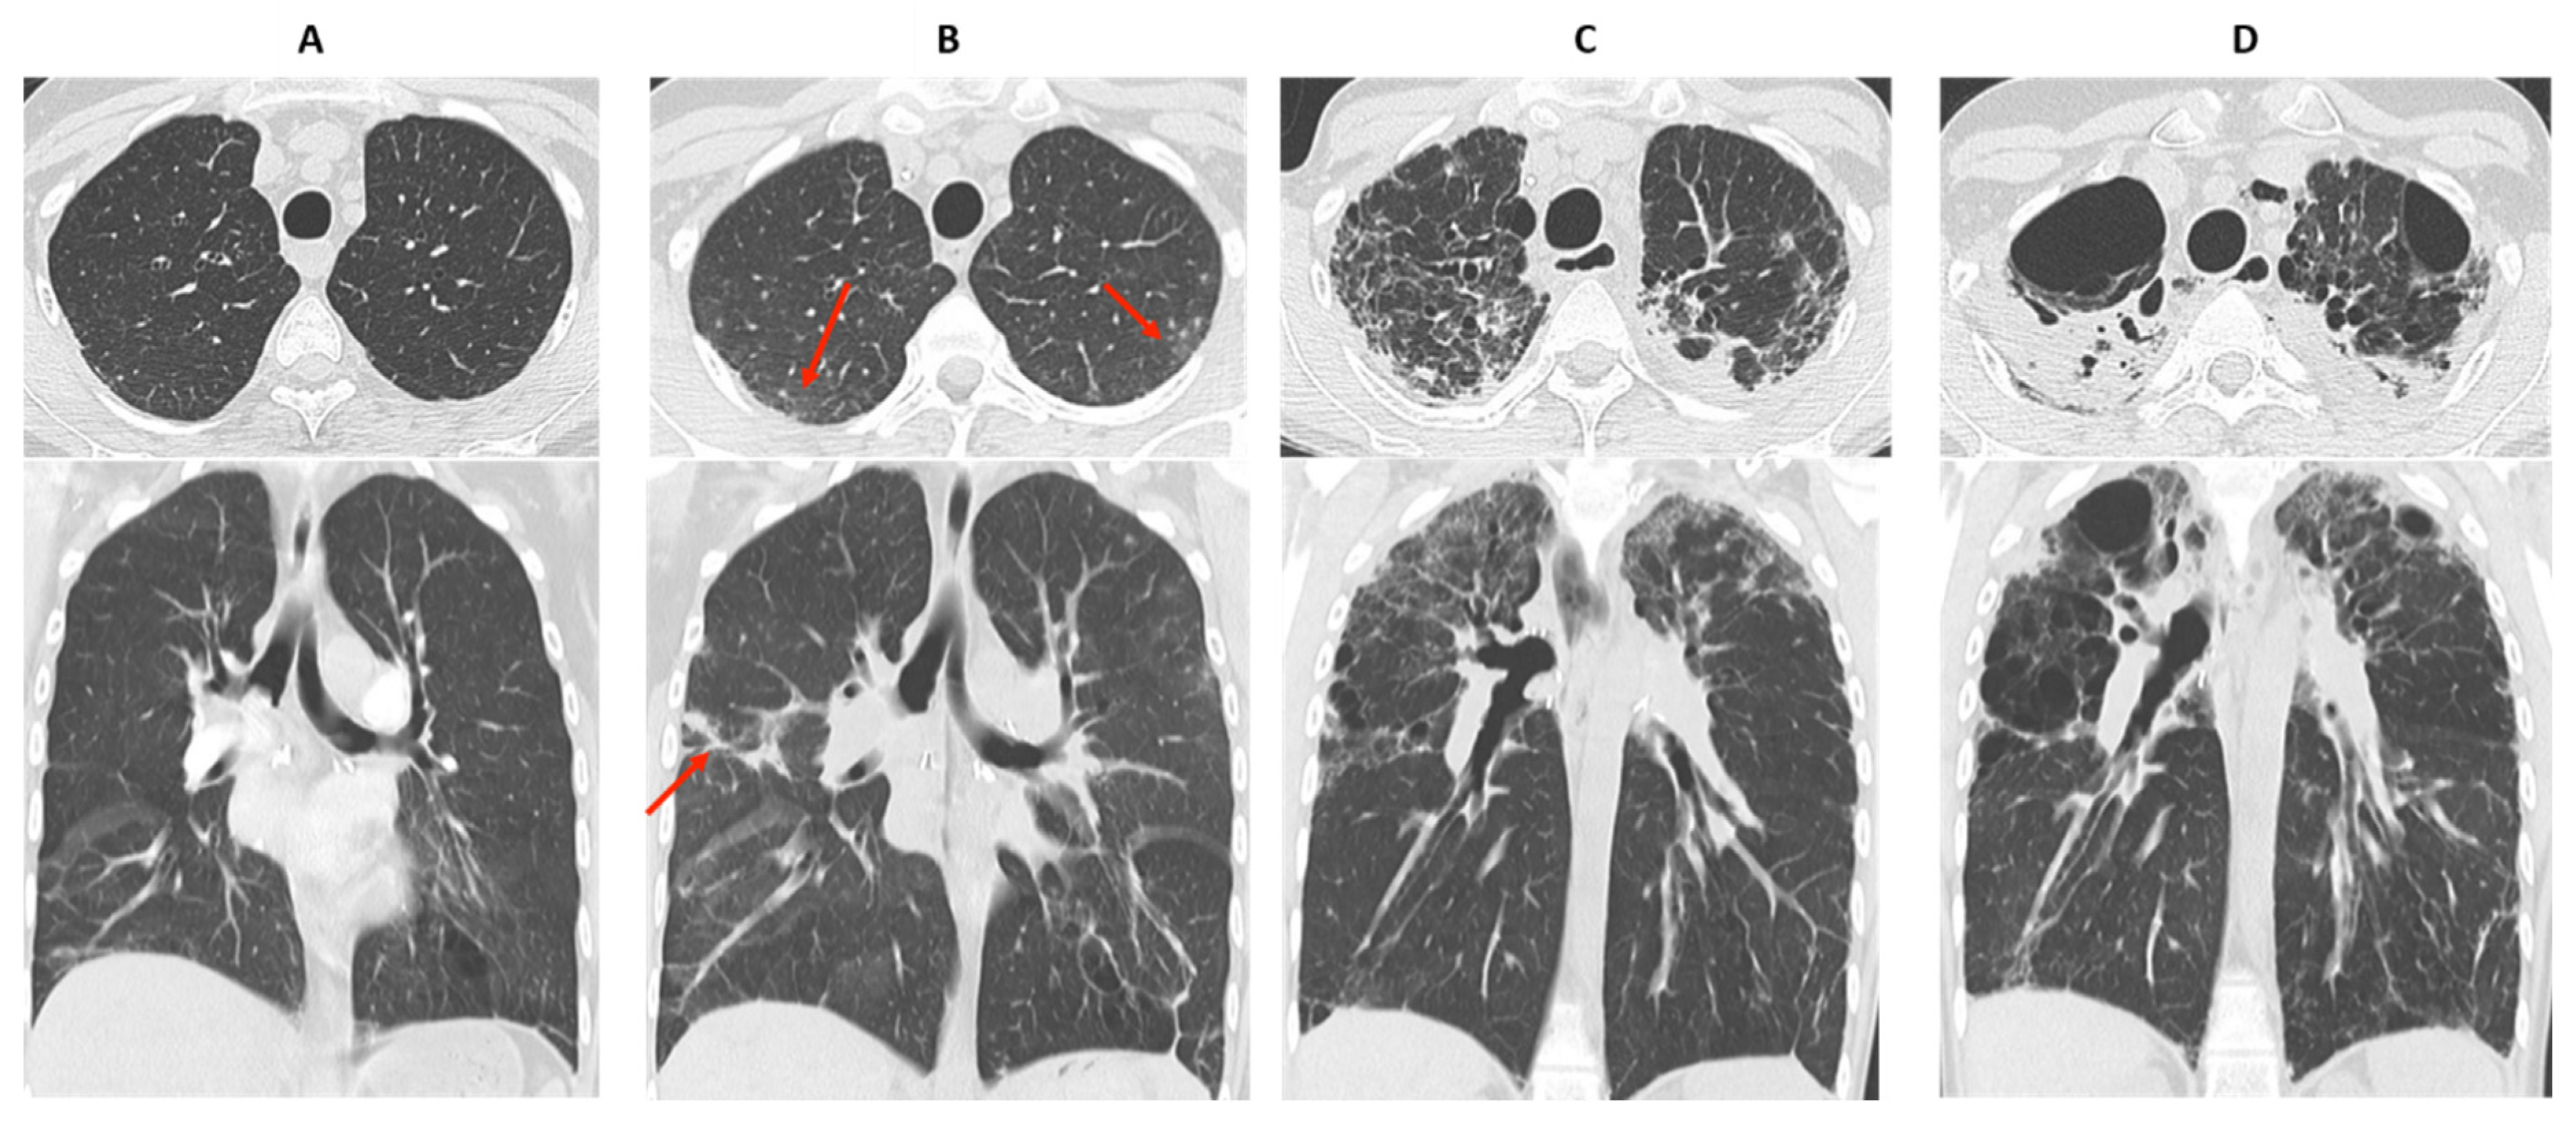

- Verleden, S.E.; Von Der Thüsen, J.; Van Herck, A.; Weynand, B.; Verbeken, E.; Verschakelen, J.; Dubbeldam, A.; Vanaudenaerde, B.M.; Vos, R.; Verleden, G.M.; et al. Identification and characterization of chronic lung allograft dysfunction patients with mixed phenotype: A single-center study. Clin. Transplant. 2020, 34, e13781. [Google Scholar] [CrossRef]

- Byrne, D.; Nador, R.G.; English, J.C.; Yee, J.; Levy, R.; Bergeron, C.; Swiston, J.R.; Mets, O.M.; Muller, N.L.; Bilawich, A.-M. Chronic Lung Allograft Dysfunction: Review of CT and Pathologic Findings. Radiol. Cardiothorac. Imaging 2021, 3, e200314. [Google Scholar] [CrossRef] [PubMed]

- Dettmer, S.; Shin, H.-O.; Vogel-Claussen, J.; Westphal, M.; Haverich, A.; Warnecke, G.; Welte, T.; Wacker, F.; Gottlieb, J.; Suhling, H. CT at onset of chronic lung allograft dysfunction in lung transplant patients predicts development of the restrictive phenotype and survival. Eur. J. Radiol. 2017, 94, 78–84. [Google Scholar] [CrossRef] [PubMed]

- Sato, M.; Hwang, D.M.; Waddell, T.K.; Singer, L.G.; Keshavjee, S. Progression pattern of restrictive allograft syndrome after lung transplantation. J. Heart Lung Transplant. 2013, 32, 23–30. [Google Scholar] [CrossRef]

- Verleden, S.E.; de Jong, P.A.; Ruttens, D.; Vandermeulen, E.; Van Raemdonck, D.E.; Verschakelen, J.; Vanaudenaerde, B.M.; Verleden, G.M.; Vos, R. Functional and computed tomographic evolution and survival of restrictive allograft syndrome after lung transplantation. J. Heart Lung Transplant. 2014, 33, 270–277. [Google Scholar] [CrossRef] [PubMed]